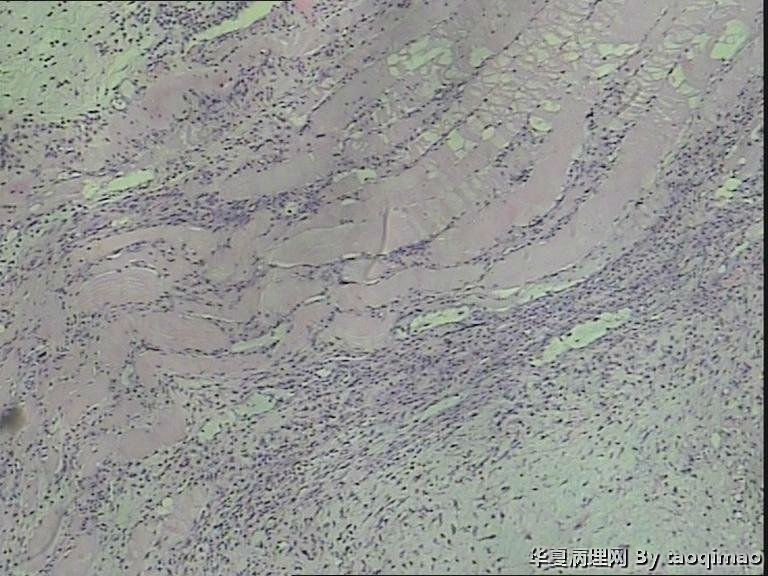

胸壁肿物

结节性筋膜炎+神经节样细胞+肌肉浸润=增生性肌炎。

粗略看了下,对软组织病变不是很在行,初步印象是增生性肌炎,几个图像里小血管内皮肿胀,周围炎细胞浸润,结合临床除外血管炎或者自身免疫相关疾病。

男,54岁,右侧胸壁肿物发现1月余,取材:灰白色不规则组织一块2*1.7*0.5cm,剖面实性灰白色,质韧。